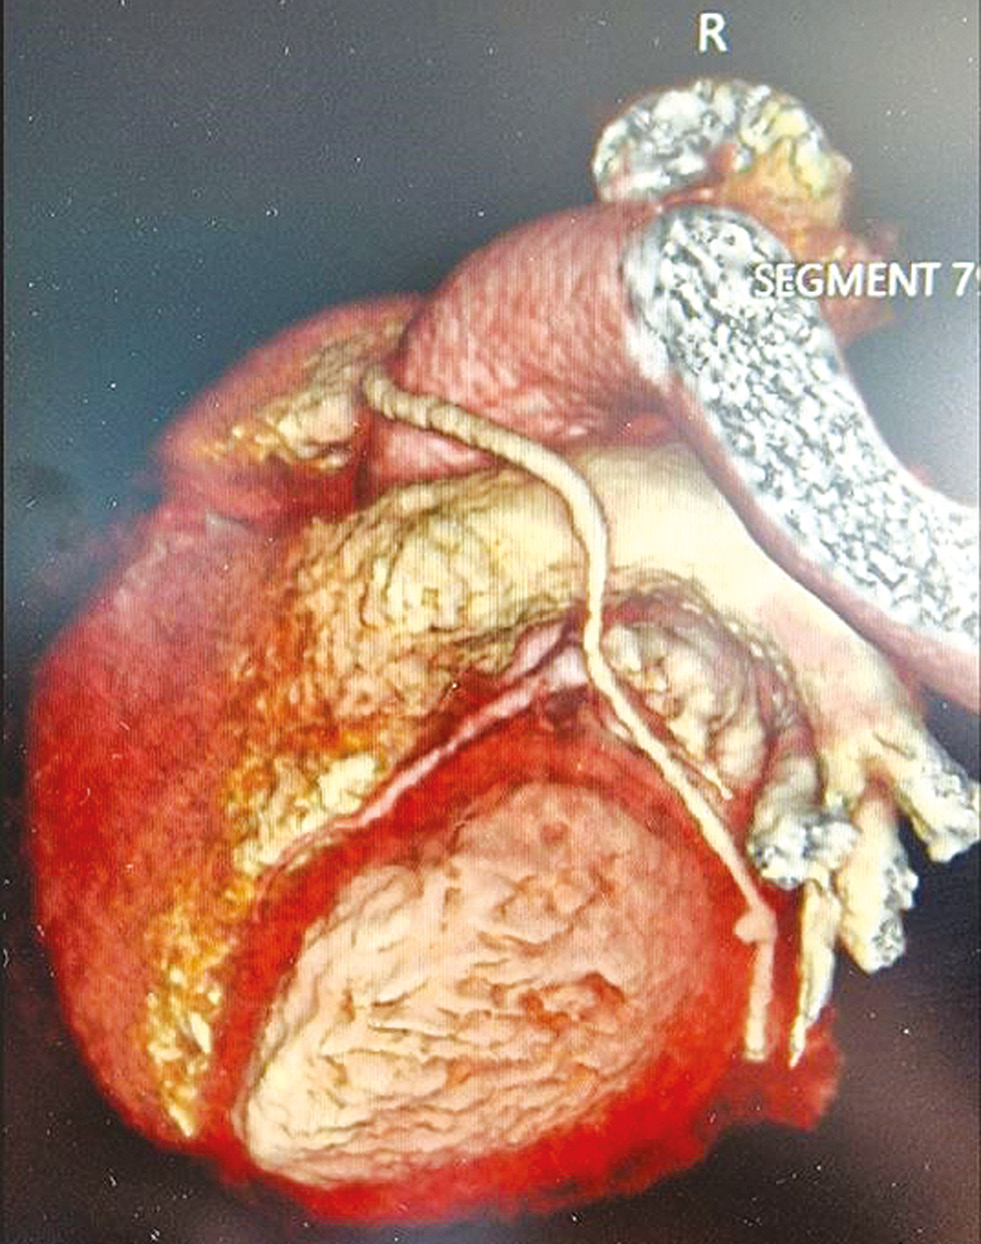

В условиях комбинированного эндотрахеального наркоза выполнена левобоковая мини-торакотомия с одномоментным забором большой подкожной вены с правой голени. Выделены левые общая бедренная артерия (ОБА) и общая бедренная вена (ОБВ), после их канюляции начато ИК. Мобилизована восходящая аорта, установлены плегическая канюля, зажим на аорту. Проведена антеградная неселективная калиево-кровяная кардиоплегия по Калафиори. ЗМЖА – неизменённая, мягкая, диаметром 2 мм. Вскрыт просвет ЗМЖА на границе средней и дистальной третей. Сформирован анастомоз аутовены с ЗМЖА по типу «конец-в-бок» непрерывным обвивным швом нитью Prolene 8-0. Анастомоз герметичен. При проведении гидродинамической пробы сброс по шунту удовлетворительный. ОА в средней трети выраженно атеросклеротически изменена, в дистальной трети – мягкая, диаметром 2 мм. Вскрыт просвет ОА на границе средней и дистальной третей. Вскрыт просвет аутовены к ЗМЖА для выполнения секвенциального шунтирования. Сформирован анастомоз аутовены с ОА по типу «бок-в-бок» непрерывным обвивным швом нитью Prolene 8-0. Анастомоз герметичен. Снят зажим с аорты. Выявлена фибрилляция желудочков. Синусовый ритм восстановлен после дефибрилляции. Выполнено боковое отжатие восходящей аорты. Плегическое отверстие расширено при помощи выкусывателя. Сформирован проксимальный герметичный анастомоз аутовены с аортой по типу «конец-в-бок» непрерывным обвивным швом нитью Prolene 6-0. Снят зажим с аорты. Снижена производительность и остановлено ИК. Введён протамин. Проведена деканюляция ОБВ и ОБА. Перикард частично ушит. После тщательного гемостаза и установки двух дренажей в правую плевральную полость выполнено послойное ушивание раны. Пациент гемодинамически стабилен, переведён в отделение реанимации. Ишемия миокарда – 59 мин, ИК – 125 мин. Время операции составило 270 мин, кровопотеря – около 300 мл (рис. 1).

Рис. 1. Компьютерная томограмма (3D-реконструкция) после секвенциального аутовенозного аортокоронарного шунтирования огибающей артерии, задней межжелудочковой артерии из мини-торакотомии (MICS CABG).